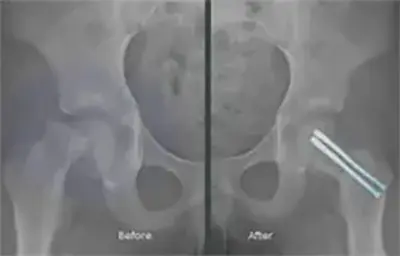

- X-rays: Detect slippage or growth plate abnormalities

- Closed reduction and internal fixation with percutaneous screw placement